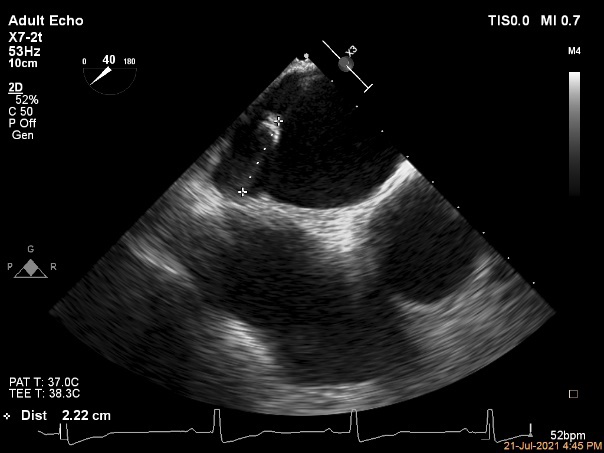

术中超声引导:

确定房间隔穿刺点:靠后

穿刺点高度测量:4.14cm

2D视图下测量大鞘长度2.2cm

2D视图下建立trajectory